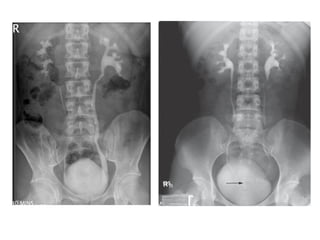

Sistema Urinário Órgãos que produzem, coletam e eliminam a urina.  Rins, ureteres, bexiga e uretra.

Sistema Urinário Órgãosque produzem, coletam e eliminam a urina. Rins, ureteres, bexiga e uretra.